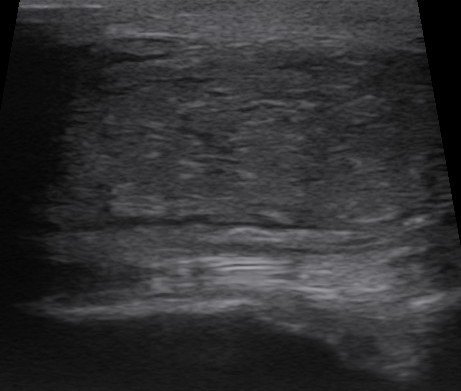

Ultraljud 2

Ultraljud är bra för att undersöka mjukdelar. Vid andra ultraljudet syns senorna tydligare och de ser fina ut. Foto: Sofia Petersson

Under den följande veckan minskar svullnaden något, men en tydlig avgränsad förändring finns fortfarande kvar över framknäet. Vi väljer därför att göra ett uppföljande ultraljud. Den här gången syns senorna tydligare, och de ser fina ut. Dessutom ser vi att svullnaden har börjat organisera sig, vilket ytterligare stärker misstanken om en blödning som håller på att läka.